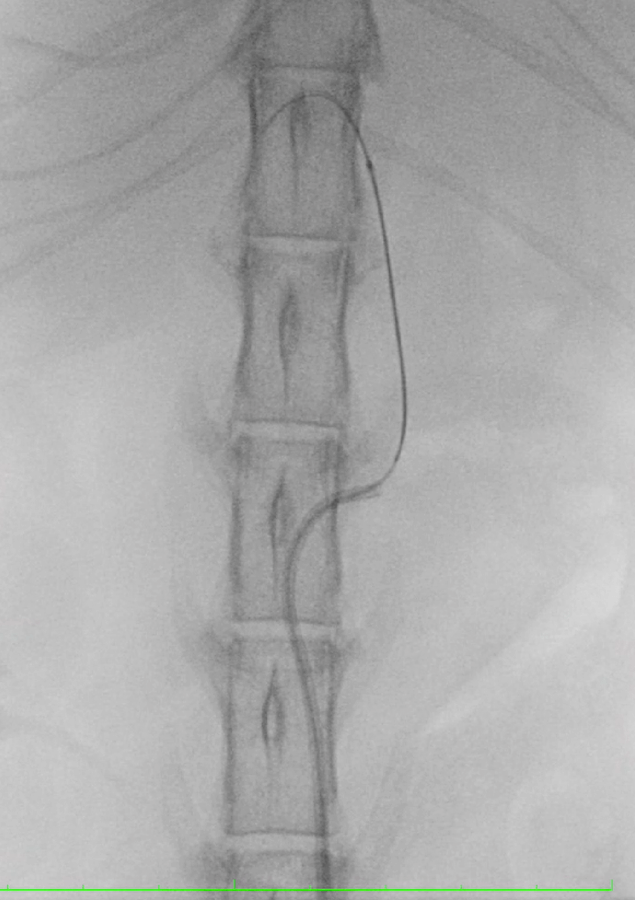

【実施症例】骨盤腔腫瘍に対する動注療法

雑種犬, 11歳, 雄。

摘出手術後に再発した肛門周囲腺癌。腫瘍は骨盤腔内まで浸潤し、再度の外科的切除は困難であった。 左総頸動脈からカテーテルを左内腸骨動脈まで挿入し、腫瘍陰影を確認。抗がん剤および塞栓剤を注入した。 実施後、腫瘍は1/4以下に縮小し正常な排便が維持できている。

骨盤腔のX線透視像